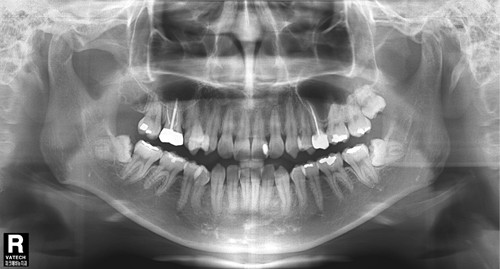

파크에비뉴치과 사랑니 발치 전 후 비교

위 두 환자는 교정치료를 위한 공간확보가 필요하여 사랑니 발치를 하게 되었다. 아래턱에 점선으로 표시 되어있는 하치조신경 다발이 사랑니 뿌리에 근접하여 지나가서 난이도가 높은 수술이었지만 3차원적 영상인 CT와 Panorama X-ray를 정밀 분석하여 발치 한 결과 신경 손상 없이 발치 할 수 있었다. 또한 두 환자 모두 “PRF(자가골성장인자)”를 이용해 사랑니 발치를 하여 부작용을 최소화 하였다.